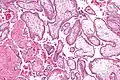

Micrograph showing chorionic villi. Intermediate magnification. H&E stain.

The bulk of the villi consist of connective tissues that contain blood vessels. Most of the cells in the connective tissue core of the villi are fibroblasts. Macrophages known as Hofbauer cells are also present.